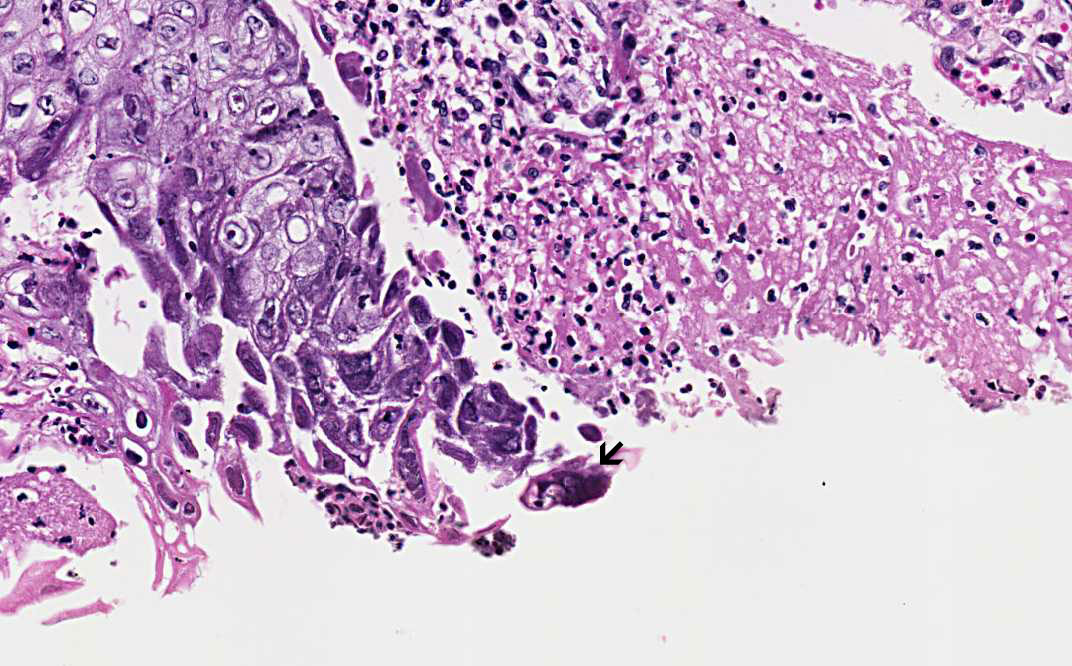

Hematoxylin & eosin

High-magnification: This image is taken from a different case and at a higher magnification (60x). The 3M nuclei (molding, margination of chromatin, multinucleated) are well demonstrated.